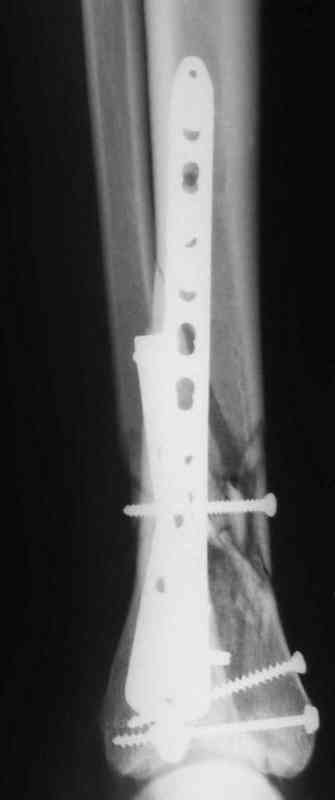

Да кстати нашёл похожий случай для пилона.Малоинвазивная дистальная пластина LCP у вас я думаю есть опыт их использования ну очень хорошая. Очень стабильно получается.